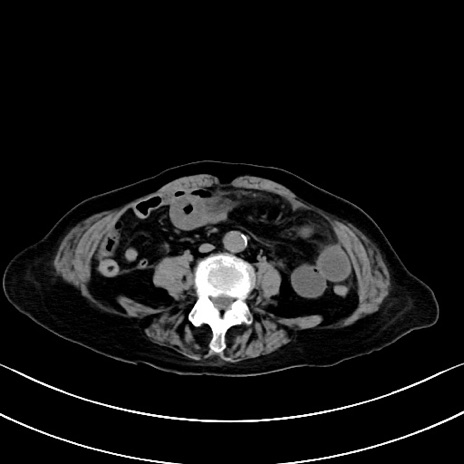

症例40(横断像)他院1日前

横断像